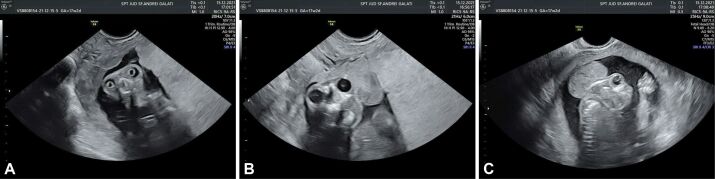

眼轮畸形是一种胎儿畸形,其特征是眼眶和睫状上脊上方的小腿完全或部分缺失。这种畸形的确切机制尚无定论,但发育第四周间质迁移紊乱是最常见的记录。尖头畸形的主要声像图特征是无小腿和大脑背侧隆起(米老鼠头)。由于颅骨的正常骨化过程,只有在妊娠 11 周后才能确诊。早期发现极为重要。预后极差,因此选择终止妊娠是首选的治疗方法。本文将根据一例妊娠晚期诊断病例,讨论我们所了解的胎儿颅骨畸形的病因和超声特征。

Acrania is a fetal malformation characterized by complete or partial absence of the calvaria above the orbits and supraciliary ridge. No exact mechanism is demonstrated for this anomaly but disturbances in mesenchymal migration during the fourth week of development are the most documented. The key sonographic features of acrania are absent calvaria and dorsally bulging brain (Mickey Mouse head). Due to the normal process of ossification of cranial bones, the diagnosis can be established only after 11 weeks of gestation. Early detection is extremely important. The prognosis is extremely poor so elective termination of pregnancy is the treatment of choice. In this paper, we discuss the things we know about pathogeny and ultrasonographic features of fetal cranial malformations based on a case diagnosed late during gestation.